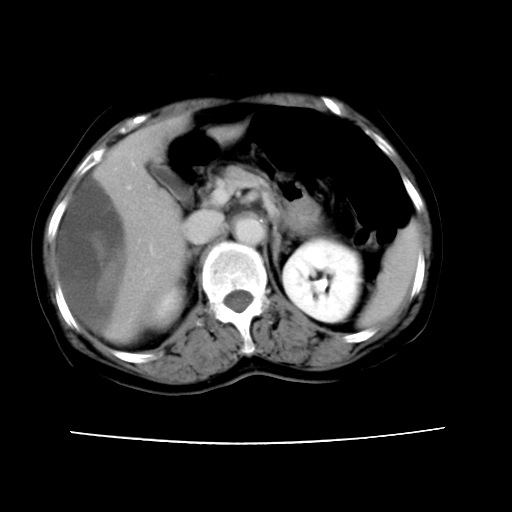

2008-11-10ct平扫(其间去中山医院诊治未行特殊治疗)

2008-11-10ct平扫见并肝内、血膜下血肿基本吸收,肝内低密度灶缩小。此时再做增强ct应有显着意义。对患者/医者都好!

从平扫+增强及治疗后复查片,病变明显缩小,不考虑肝癌出血可能,还是考虑为良性病变可能性大;单纯血肿并包膜下积液吧,病变强化没法解释,肝血管破裂出血吧,增强不符合典型血管瘤的表现,良性肿瘤破裂出血吧,复查片看来好像也不太支持(没做强化也不太好说)。本人还是考虑单纯肝内血肿并包膜下积液,强化是不是血管有外渗。

患者自6月至11月,如果是肝癌,没有经过特殊治疗,想必应该会有所进展吧,而不是ct所见,反而似有病灶减小的趋势。建议增强。